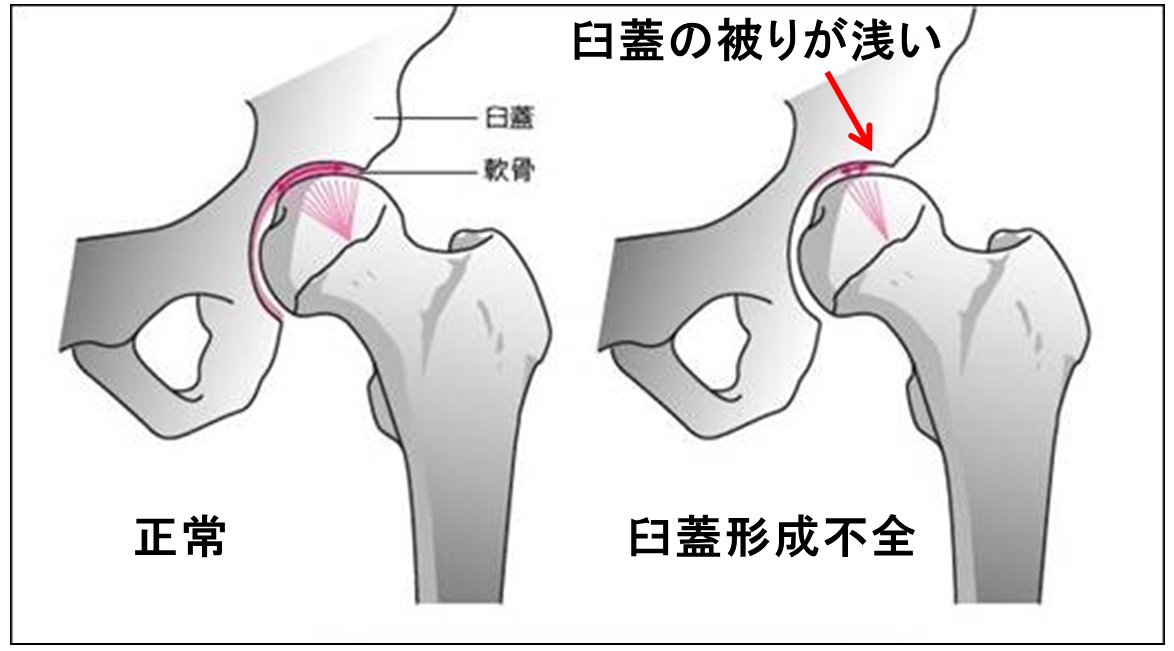

肩の関節もそうなのですが、股関節はよく受け皿とボールの関係性だと言われています。受け皿が寛骨臼蓋でボールの役割が大腿骨頭になります。寛骨臼蓋の向きは前側で且つ外側に向いているため、大腿骨頭は全部受け皿の中にかぶっているよりも、少しはみ出しているイメージをしていただくとよろしいかと思います。

股関節でお悩みにならている方は大腿骨頭の頚体角、もしくは前捻角に問題が生じていたり、臼蓋に問題が起きていることが一般的に考えられます。

これらの要素を踏まえて、どのような運動をするか考慮しないで、「とにかく筋肉をつける」だけに着目しすぎたら、気づいた頃には股関節症の進行が進んでいた、なんてこともあるかもしれないので、運動をする前に股関節の構造の理解から入ると解決の糸口も見つけられるかもしれませんので、お勧めです。